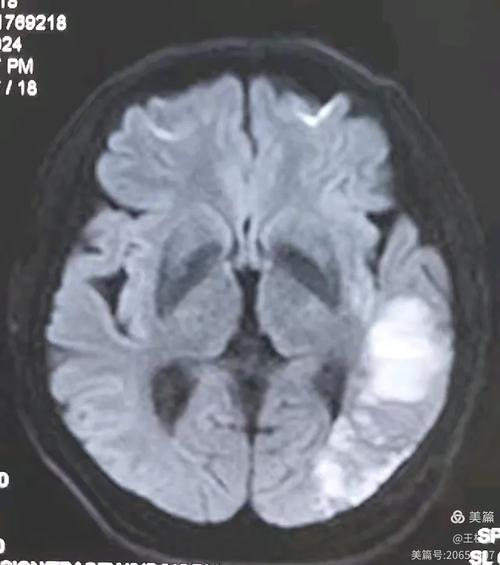

DWI序列(弥散加权成像)—— “脑梗的照妖镜”

这是诊断急性脑梗最最关键的序列。

- 图片表现:在正常的脑组织背景上,梗死的区域会显示为一个非常亮的白色高信号。

- 原理:急性梗死的脑细胞水肿,细胞膜破裂,细胞内的水分子运动受到极大限制,无法自由“弥散”,DWI序列对水分子的自由运动非常敏感,运动受限的区域信号就异常增高,呈现出亮白色。

- 临床意义:只要在DWI上看到明确的亮白斑,医生就可以高度怀疑是新鲜的脑梗死,并立即进行溶栓或取栓等治疗,这是时间窗内(通常发病后4.5-6小时内)决定治疗的关键依据。

示例图(模拟):

(图片来源网络,侵删)

- 左侧是正常的DWI图像,脑组织信号均匀。

- 右侧是急性脑梗患者的DWI图像,红色箭头所指的白色高信号区域就是急性梗死灶。